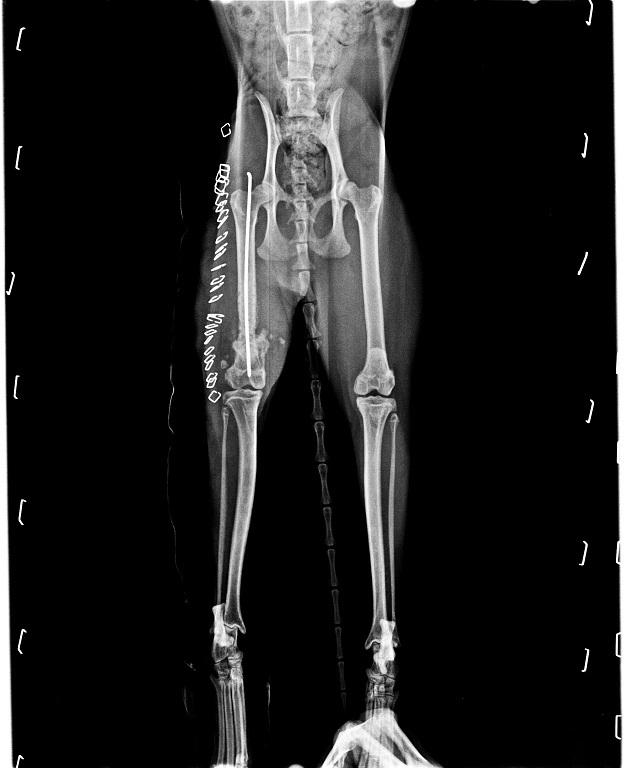

5/27住院

小久已經拆除了腳上固定用的繃帶,

外科方面已經大致完成治療,

但內科方面仍有許多難題需克服 (細菌感染)。

6/1住院

小久這幾天因為骨釘外露的關係,

醫生只能先將骨釘拔出,

雖然只是約10分鐘左右的小型手術,

但包覆骨頭的肌肉組織癒合問題讓醫生們蠻頭痛。

6/8住院

在小久住院觀察期間裡,

醫生發現小久的後腿有神經受損的問題,

伸直站立是沒有問題的,

但要坐下時較難正常地反應,

需要時間慢慢復健。

6/15出院

小久已經在醫院治療好絕大部分的病症,

包括自高樓墜下造成的前腳骨折,

其他還有寄生蟲、耳疥蟲、黴菌、血尿、上顎裂、下巴損傷等等,

大致都已經痊癒,

只剩下後腿神經損傷需要慢慢復健而已。